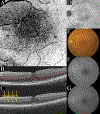

Purpose: To describe the appearance of concentric, fingerprint-like waves within the Henle fiber layer (HFL) using en face optical coherence tomography in patients with tractional pathologies of the retina.

Results: Optical coherence tomography data from six patients with tractional vitreoretinal pathology were reviewed. Concentric, fingerprint-like microwaves were visualized through en face optical coherence tomography in all six study eyes at the level of the HFL. This finding resembled the finding of HFL waves previously noted histopathologically from force exerted on this layer.

Conclusion: In retinal pathologies in which specific physical forces act on the retina, volumetric optical coherence tomography may permit visualization of en face concentric, fingerprint-like hyperreflective rings within the HFL. This "fingerprint sign" may represent a biomechanical consequence of traction on the retina and allow clinical decision making based on improved recognition of the existence of such traction.